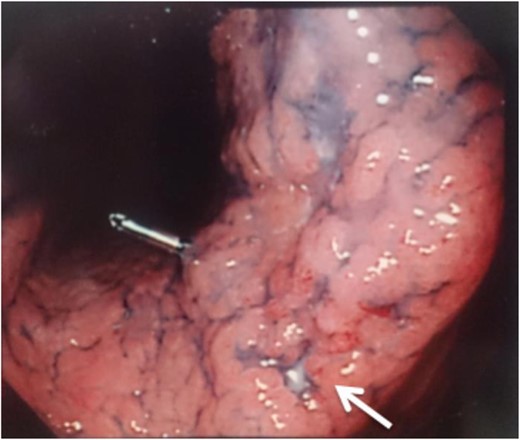

Two years and 3 months after esophagectomy, he complained of pain in the left shoulder. A mass was found between the trapezius and supraspinatus on CT and magnetic resonance imaging (Fig. 3). 18F-fluorodeoxyglucose (FDG) positron emission tomography (PET) demonstrated increased levels of FDG accumulation in the left shoulder. Needle biopsy demonstrated class V (unclear type of carcinoma) disease. Therefore, we performed tumor dissection for muscle metastasis, and the histopathologic diagnosis was SCC. The patient thus underwent adjuvant chemotherapy with S-1 (80 mg/day) administered 4 weeks on/2 weeks off schedule for 1 year.